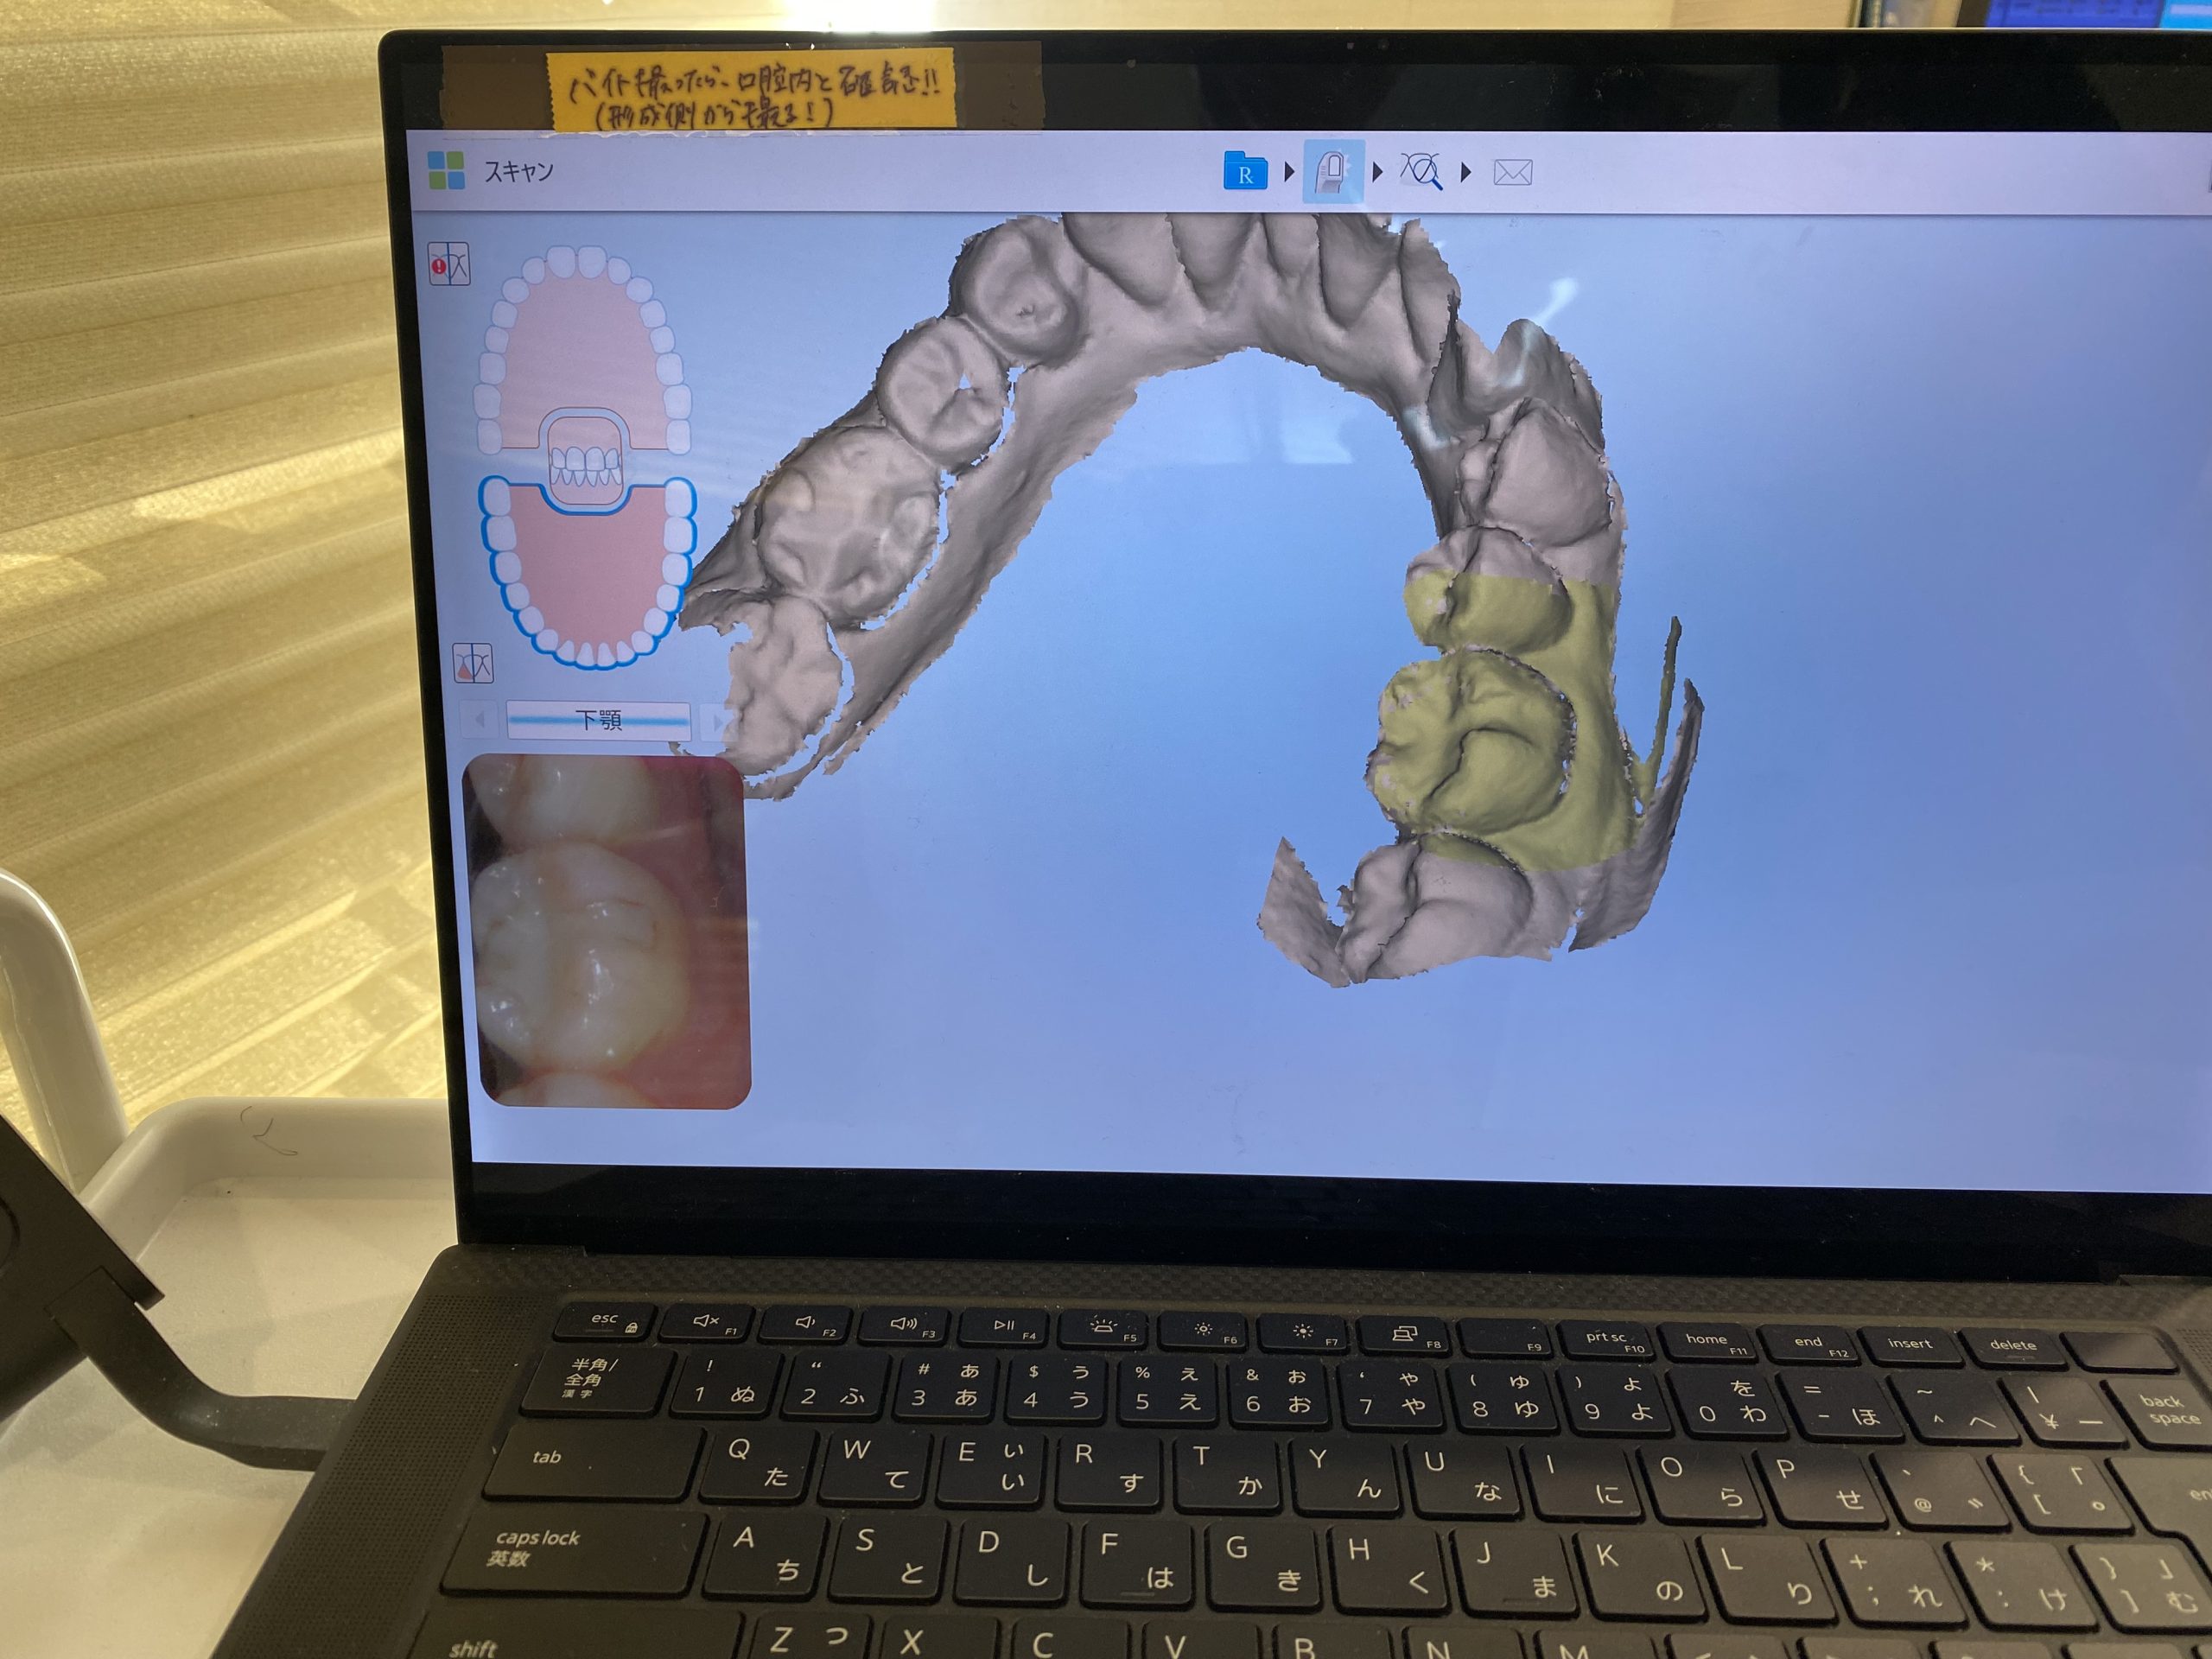

3Dスキャナーで一歩先を行く診療を実現 2022.1.1

マウスピース矯正、インビザラインの矯正装置を作製する時『iTero Element(アイテロ エレメント)』という3Dスキャナーで採取しています。

今までは『シリコン印象』という精密印象材で、型をとるため嘔吐反射がある方は特に大変でした。

この『iTero』の導入で快適にしかも精密に歯型をとることができます。

これまではシリコン印象した歯型をアメリカまで空輸していたのですが、今ではデータをインターネットで送りますので1~2週間も早く治療をスタート出来るのです。

単なる口腔内スキャナーではなく

・3Dデジタル印象、ジルコニアなどの補綴物の型取りも行います

・口腔内カラー写真

・経時的変化を記録することで患者様により理解して頂けます

・嚙み合わせの強い所、弱いところなどの咬合診断

・隣接面の虫歯の発見

・歯がどのように動いていくかのシュミレーションシステム

・もちろん口腔内カメラとしても使えますが、なんと言っても放射線照射なしなのです。

近赤外光画像(NIRI)技術で歯の内部構造をリアルタイムでスキャンしデータ化します。

普通のレントゲンでは心配という患者様に早期発見に役立ちますね。

矯正だけでなく嚙み合わせが不調の方も先進的な視覚化ツールで患者様は御自身の口腔内状態についてリアルタイムで知ることができます。

私達クリニック側からも、診断と治療のワークフローがよく患者様の石膏模型もスキャンデータでクラウド上に保管できるのも助かります。

今年もどんどん進化し続けますのでどうぞよろしくお願い致します。